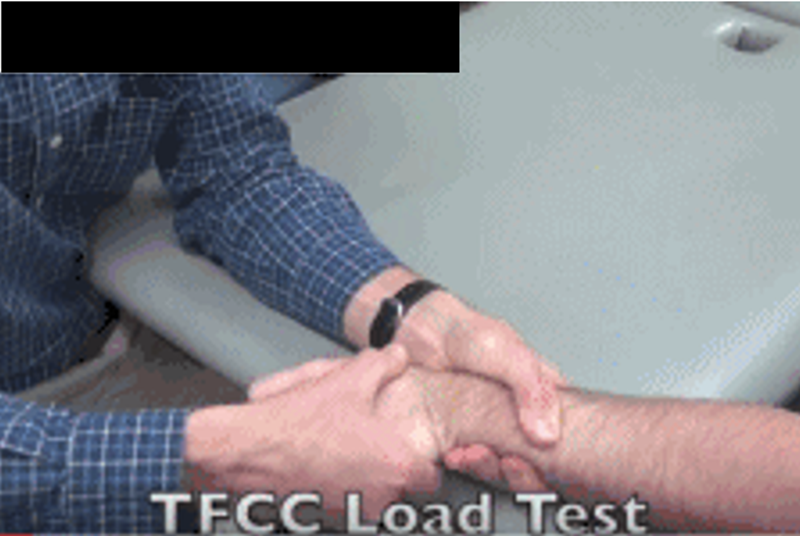

TFCC Load Test:患者坐位,检查者一只手握住患者的前臂,另一只手握住患者手部,然后沿着中轴施加力量并将手腕向尺侧偏移,同时将手腕往背侧和掌侧移动或旋转前臂。如果此测试会引起TFCC处疼痛感、有喀、啪声则测试为阳性。

图 TFCC Load Test